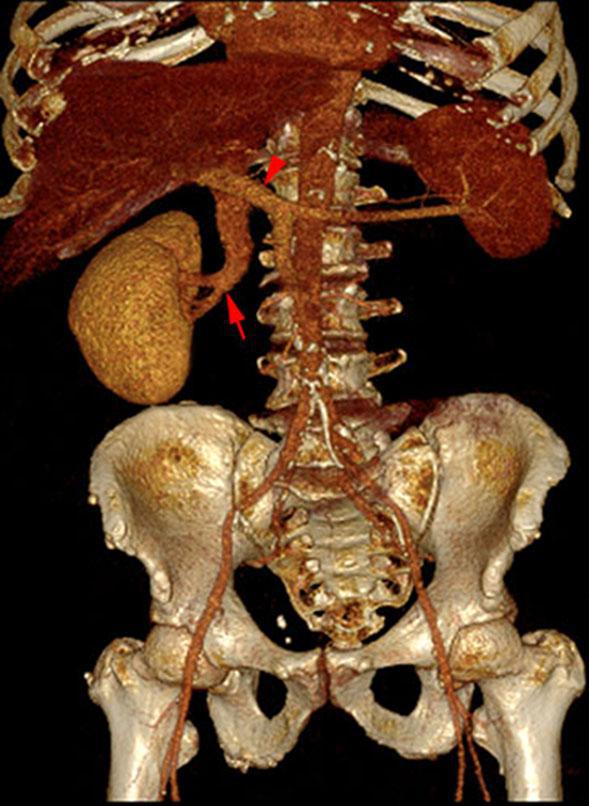

Hipoplasia renal 2